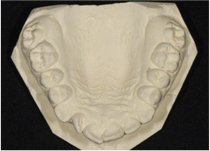

Early Orthodontics (The "Magic Window" Ages 8–10)

Starting orthodontic care young can guide jaw development, address crowding or bite issues, and sometimes reduce the need for treatment later. We recommend an assessment if your child has missing adult teeth, spacing concerns, or an over/underbite.